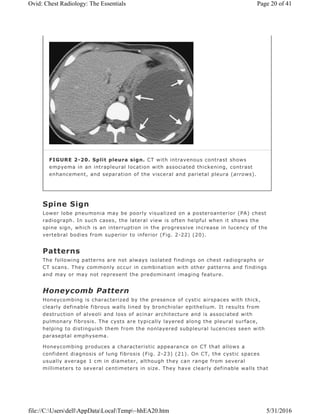

FIGURE 2-20. Split pleura sign. CT with intravenous contrast shows

empyema in an intrapleural location with associated thickening, contrast

enhancement, and separation of the visceral and parietal pleura (arrows).

Split Pleura Sign

Normally, the thin visceral and parietal pleura cannot be distinguished as two

separate structures on CT scanning. With an exudative pleural effusion, such as

empyema (Fig. 2-20), the fluid separates or “splits†the thickened and

enhancing pleural layers (18).

Spine Sign

Lower lobe pneumonia may be poorly visualized on a posteroanterior (PA) chest

radiograph. In such cases, the lateral view is often helpful when it shows the

spine sign, which is an interruption in the progressive increase in lucency of the

vertebral bodies from superior to inferior (Fig. 2-22) (20).

Honeycomb Pattern

Honeycombing is characterized by the presence of cystic airspaces with thick,

clearly definable fibrous walls lined by bronchiolar epithelium. It results from

destruction of alveoli and loss of acinar architecture and is associated with

pulmonary fibrosis. The cysts are typically layered along the pleural surface,

helping to distinguish them from the nonlayered subpleural lucencies seen with

paraseptal emphysema.

Honeycombing produces a characteristic appearance on CT that allows a

confident diagnosis of lung fibrosis (Fig. 2-23) (21). On CT, the cystic spaces

usually average 1 cm in diameter, although they can range from several

millimeters to several centimeters in size. They have clearly definable walls that

are 1 to 3 mm thick, they are air-filled, and they appear lucent in comparison to

normal lung parenchyma. Honeycombing is usually associated with other findings

of lung fibrosis, such as architectural distortion, intralobular interstitial

thickening, traction bronchiectasis, and irregular linear opacities. Honeycombing

on CT usually represents idiopathic pulmonary fibrosis,

collagen vascular disease, asbestosis, chronic hypersensitivity pneumonitis, or

drug-related fibrosis (Table 2-1).